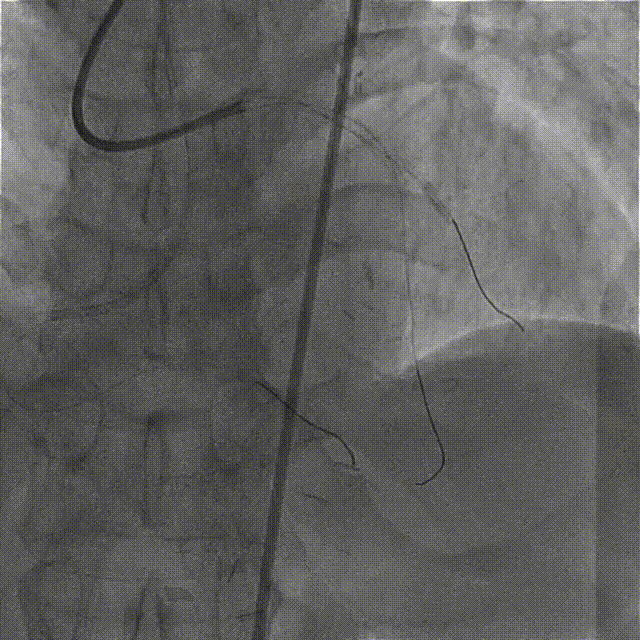

依次用Pinoeer 2.0mm x 15mm、Pinoeer 2.5mm x 15mm球囊至病变处反复扩张,送入Marvel导丝至D1远段做保护,LAD行IVUS检查。

IVUS检查示:可见导丝全程走行与血管真腔,近中段重度纤维增生斑块伴局部钙化,远段血管床废用性萎缩。

于LAD病变处由远及近依次植入XIENCE Alpine 2.5mm x 18mm和XIENCE Alpine 3.0mm x 23mm支架各一枚。